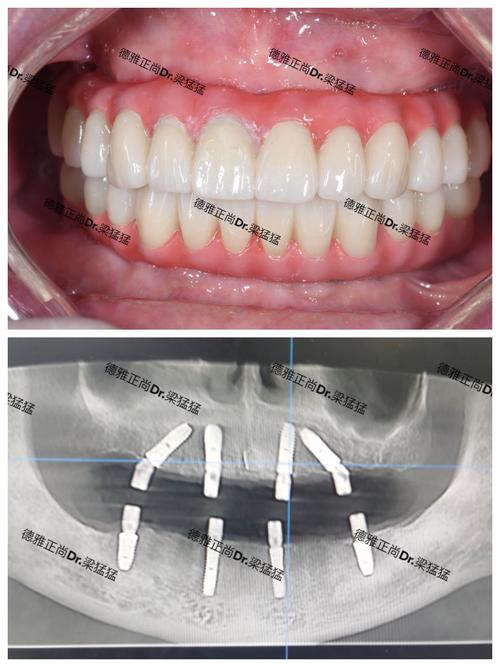

种植牙的长期成功依赖于“骨结合”(种植体与牙槽骨的紧密结合),而软组织则是保护骨结合成果的“天然屏障”,健康的牙龈能紧密包裹种植体颈部,形成生物封闭,防止细菌入侵、食物残渣堆积,避免种植体周围炎的发生,软组织的形态、色泽直接影响种植牙的美学效果,尤其是前牙区,牙龈的自然弧度、乳突形态决定了修复体是否与邻牙协调,避免“假牙感”,足够的牙龈厚度能提供良好的血供支持,促进骨结合,降低术后吸收风险。

重视软组织处理的优势显著:美学上,能模拟天然牙龈的“粉白交界线”,避免“黑三角”或“牙龈红肿”;功能上,增强咀嚼时的封闭性,防止食物嵌塞;长期来看,降低种植体周围炎风险,延长种植牙使用寿命,术后需注意:保持口腔卫生,使用软毛牙刷、冲牙器清洁种植区域;避免吸烟(尼古丁影响血供);饮食以温凉、软食为主,避免碰撞术区;定期复查,监测牙龈形态及种植体稳定性。